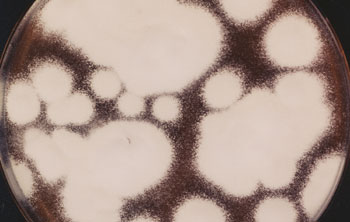

Fuß- und Nagelpilzerkrankungen werden überwiegend durch Fadenpilze (Dermatophyten) wie Trichophyton rubrum und Trichophyton mentagrophites verursacht (Letzterer hier im Bild). Für die Überlassung des Bildes und Zustimmung zur Veröffentlichung dankt die Redaktion dem mykologischen Labor der Universitäts-Hautklinik Düsseldorf und deren früherem Direktor Professor Dr. Dr. Thomas Ruzicka.

Nagelpilz entwickelt sich häufig aus einer nicht oder nicht ausreichend behandelten Fußpilzerkrankung, da er im Wesentlichen durch die gleichen Erreger verursacht wird. Dies sind überwiegend Dermatophyten, insbesondere Trichophyton rubrum und Trichophyton mentagrophites, der neuerdings auch Trichophyton interdigitale genannt wird (Abbildung).